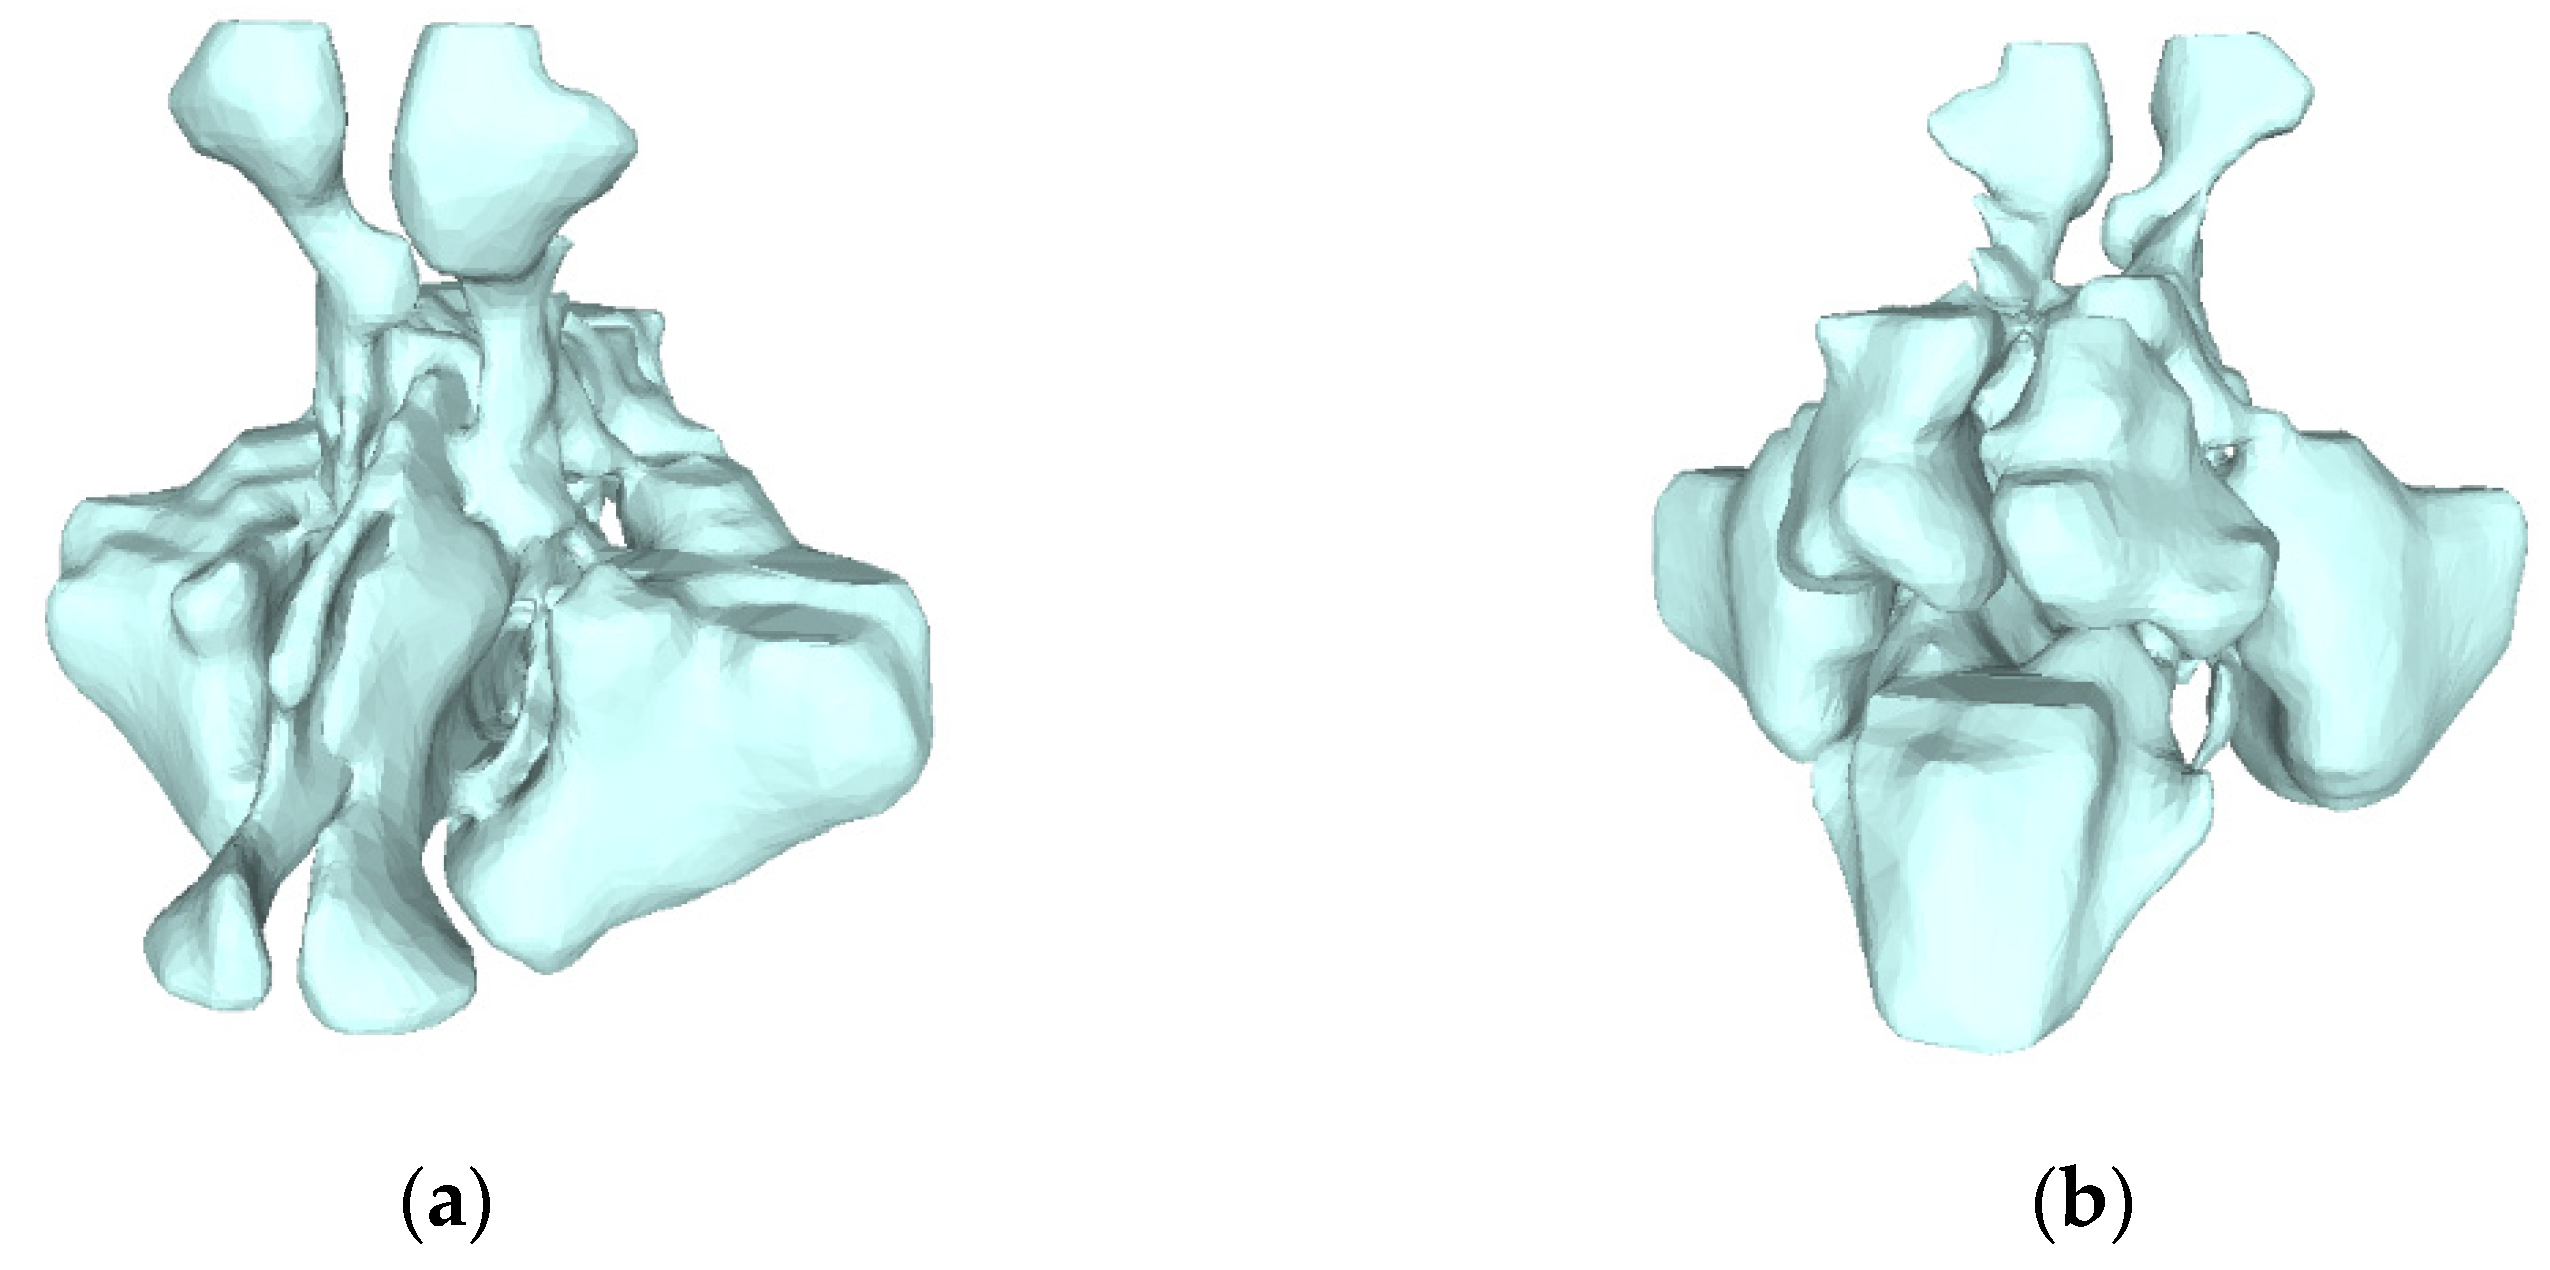

3.2. Nasal Sinus Region Segmentation

3.4. Volume Reconstruction

3.4.1. Morphology

3.4.2. 3D Reconstruction